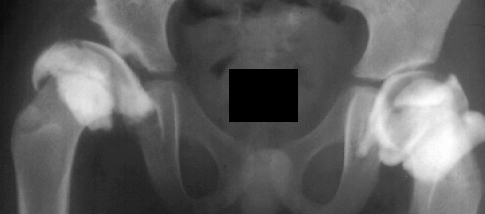

Physical exam showed the right hip to be dislocated. X-rays demonstrated

a dislocation of the right hip without the presence of an ossific nucleus

on the right side suggesting ischemic necrosis.

Following traction, open reduction was repeated, with satisfactory results;

however subsequent radiographs show an irregular pattern of growth with

a tendency for subluxation even though it was treated part time in an abduction

brace.

X-rays

and

arthrogram at two years of age show irregular ossification of the femoral

head and dysplastic acetabulum,

but the hip coverage was acceptable even in adduction.